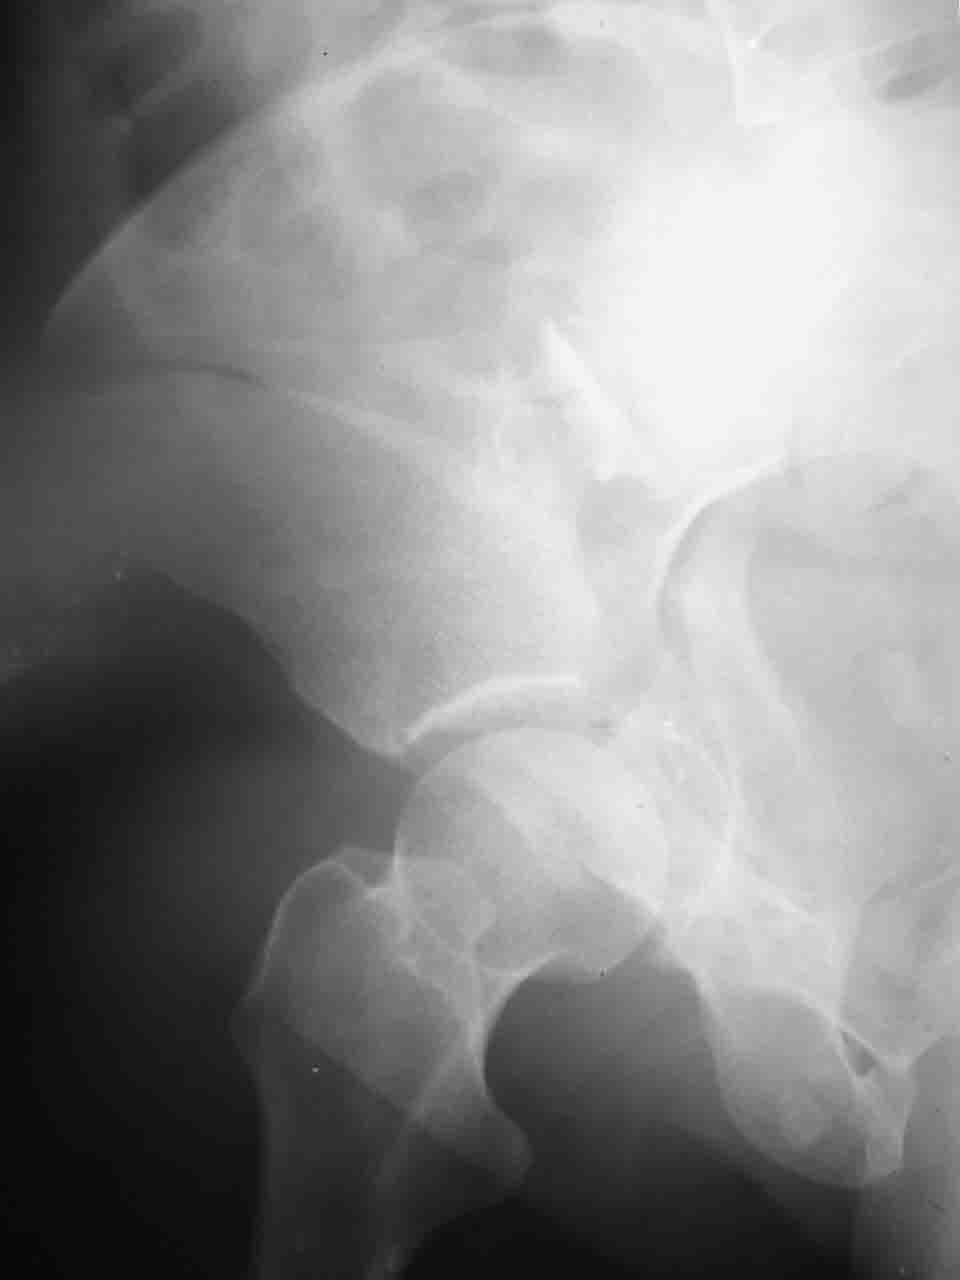

Уважаемые коллеги,43 летний мужчина, попав в автоаварию 13.10.2004, получил оскольчатый перелом обеих колонн левой вертлужной впадины.

На рентгенограммах - высокий двухколонный перелом вертлужной впадины с нарушением конгруэнтности, имеется обратная клиновидность суставной щели.

Причиной обращения к сообществу были возникшие непосредственно после операции сомнения и разочарования полученным качеством репозиции: а надо ли было трогать перелом вообще, репозиция передней колонны технически была очень сложна для меня, хотя реконструкции была в той же последовательности, что Д-р А.В.Рунков рекомендовал, в какой-то момент безуспешных манипуляций стал думать о *вторичной конгруэнтности*, которую не так давно обсуждали на

форуме и скелетном вытяжении. С репозицией и фиксацией задней колонны и отдельно задне-верхней стенки впадины проблем не возникло. Послеоп. Рг граммы в приложении. Если возникнут какие-либо дополнения или поправки - был бы признателен.